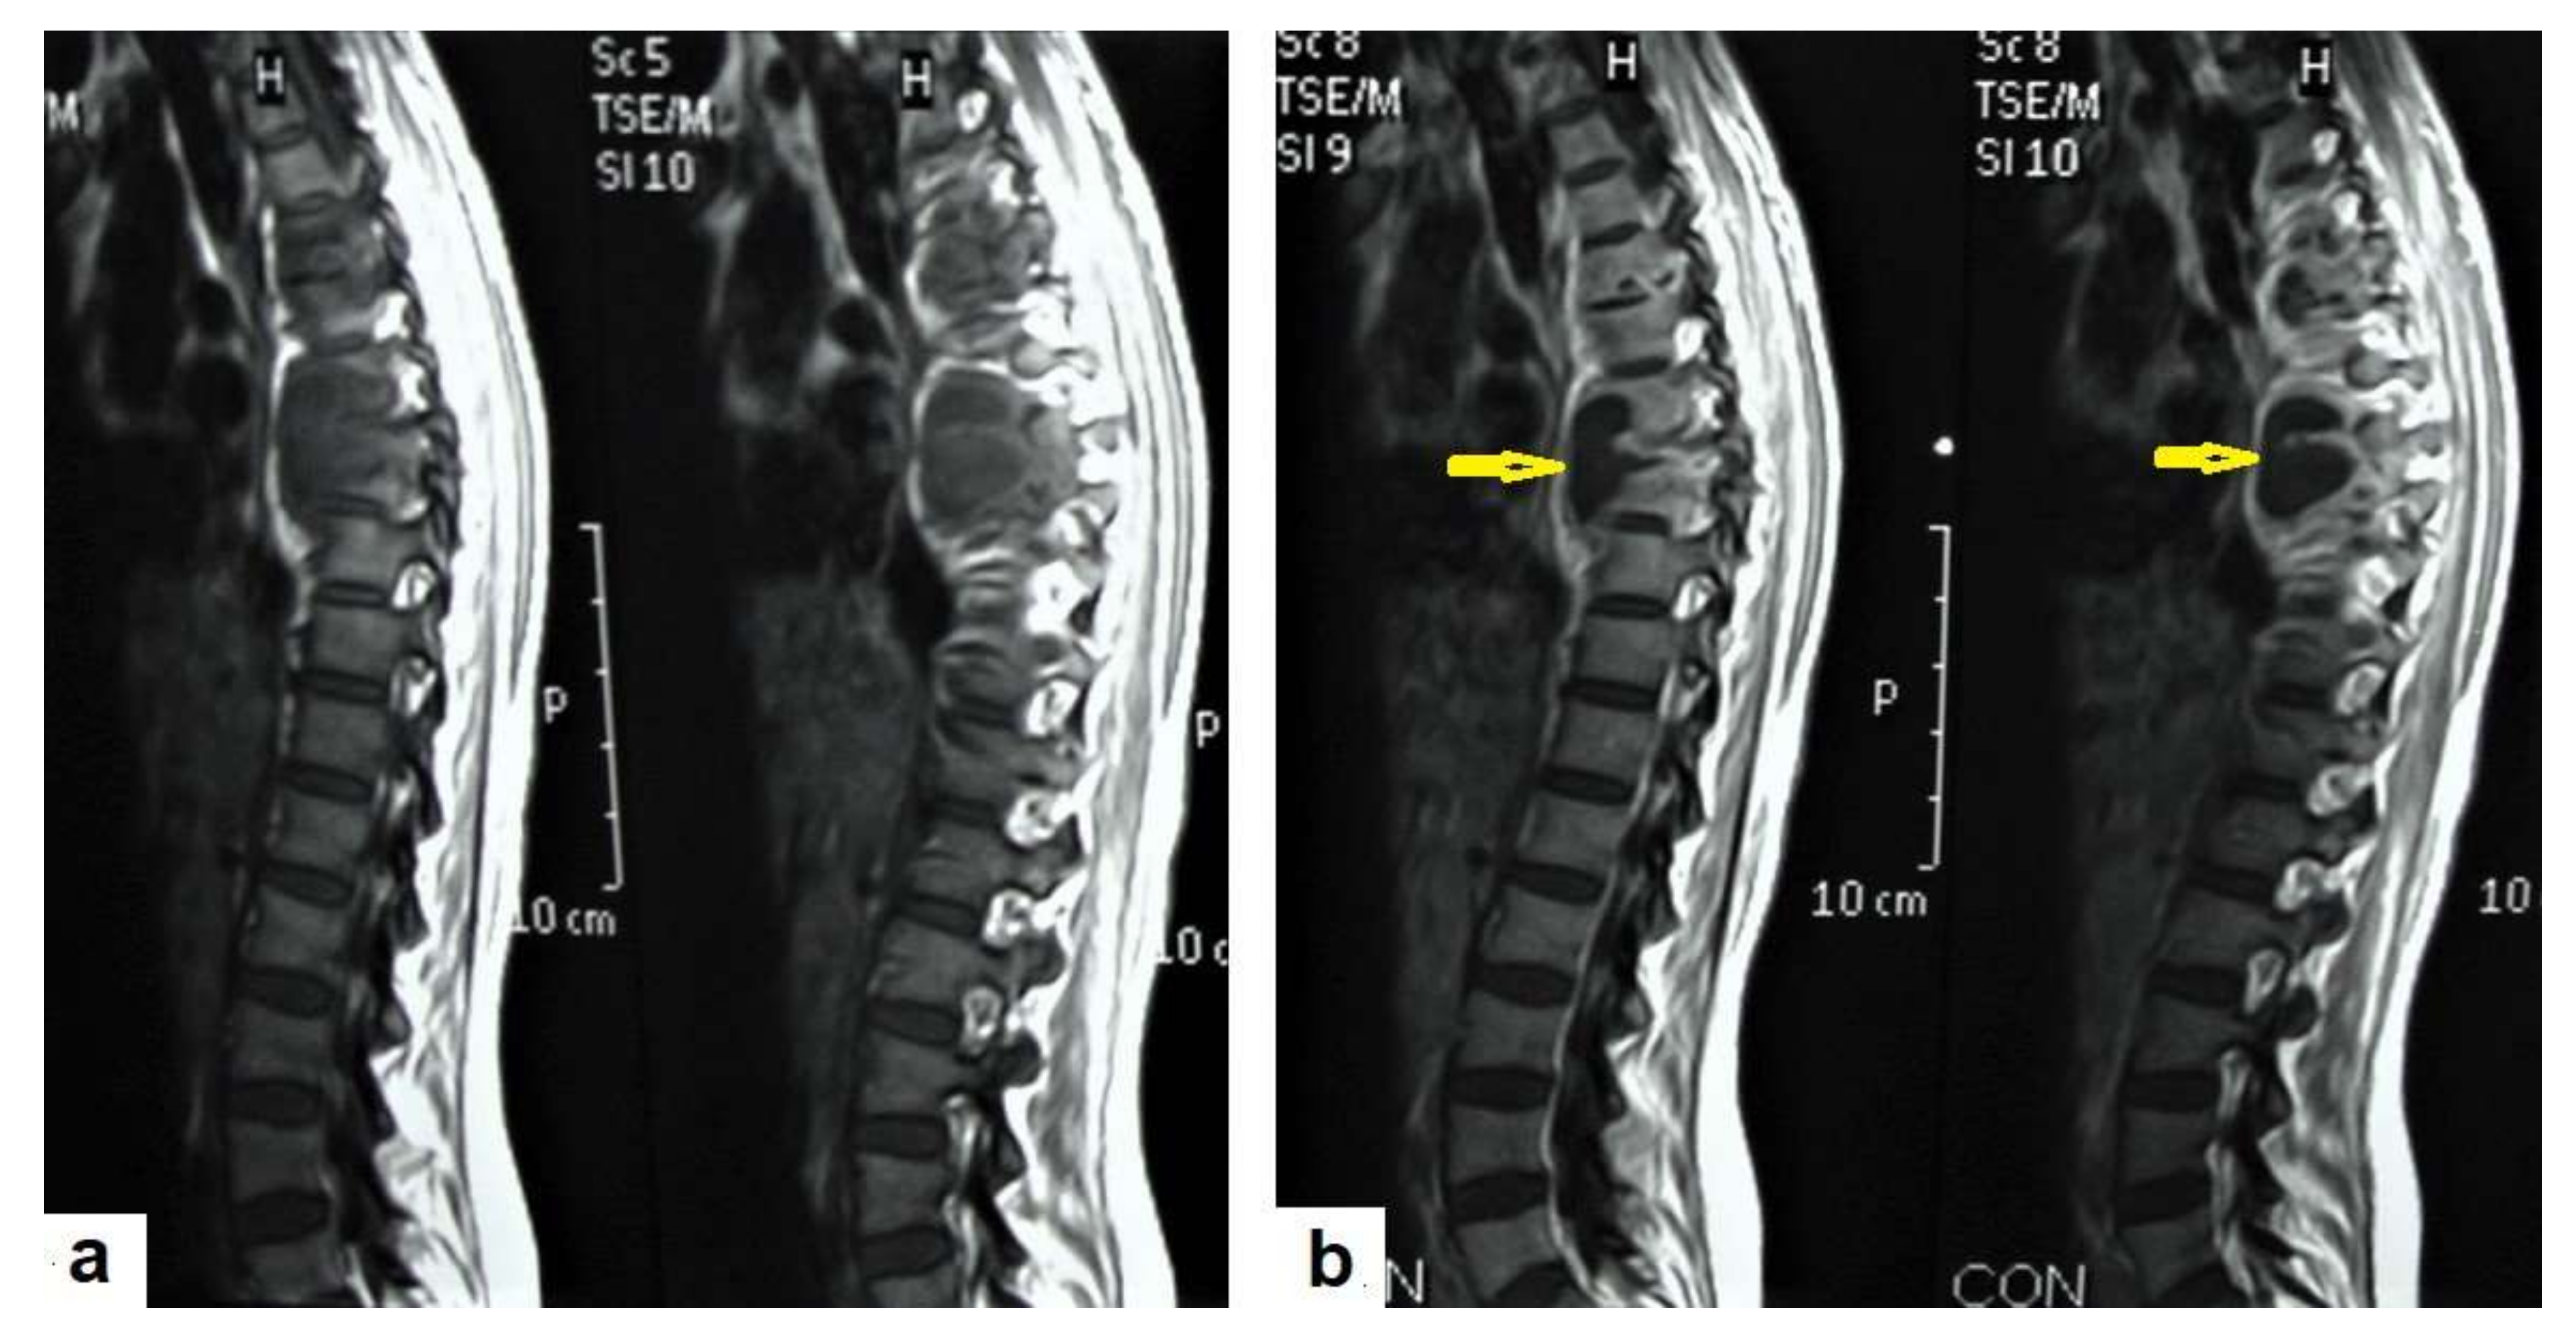

• Tuberculous spondylitis (Pott’s disease; Figure 18 and Figure 19) is a tuberculous infection of the spine that can affect any age and most commonly affects the lower thoracic and lumbar, followed by the cervical spine. It usually affects multiple contiguous vertebrae with paraspinal extension, causing subdural or epidural abscess formation and resultant spinal cord compression, which is a leading cause of paraplegia [27]. CT demonstrates the extent of bone involvement, while MRI demonstrates spinal-cord and soft-tissue involvement. Tuberculous spondylitis appears as a well-defined paraspinal abnormal signal intensity, as a thin wall abscess, or a combination of intraosseous and soft tissue abscesses. The spread of infection is sub-ligamentous beneath the anterior longitudinal ligament involving multiple vertebrae with high signal intensity on T2WIs. Pott’s disease is a difficult differential diagnosis with a spinal pyogenic infection. MRI demonstrate have 100% sensitivity, 80% specificity, and 90% accuracy in differentiating tuberculous from pyogenic spinal infection [34].

Figure 18. Pott’s disease in a 28-year-old female. Selected images of sagittal MRI of thoracic spine show destructive lesion affects multiple contiguous thoracic vertebrae with paraspinal collection. (a) Pre-contrast and (b) post-contrast T1-weighted images show subligamentous spread of the infection to involve five vertebrae with peripheral enhancement of the lesions, suggesting an abscess (arrow).

Diagnostics 12 00306 g018

Figure 19. Pott’s disease in a 6-year-old female patient. Selected images of lumbosacral MRI. Sagittal (a) T1-weighted images and (b) T2-weighted images show that destructive lesion involves the T4/T5 disc and vertebrae, with extensive pre-vertebral loculated fluid collection. Selected axial images of MRI (c) T1-weighted image with gadolinium, and (d) T2-weighted image shows bilateral paravertebral loculated fluid collections involved in bilateral psoas; paravertebral muscles appear to have low-signal-intensity contents on T1-WIs with marginal enhancement after contrast administration and high-signal-intensity contents on T2-WIs (arrows). The picture is typical of Pott’s disease with bilateral psoas and paravertebral abscesses.